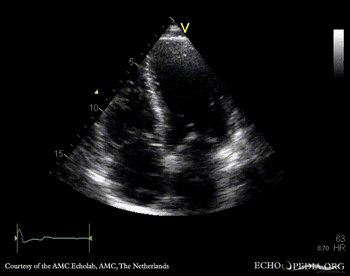

Chiari network

A4CH: Chiari network right atrium